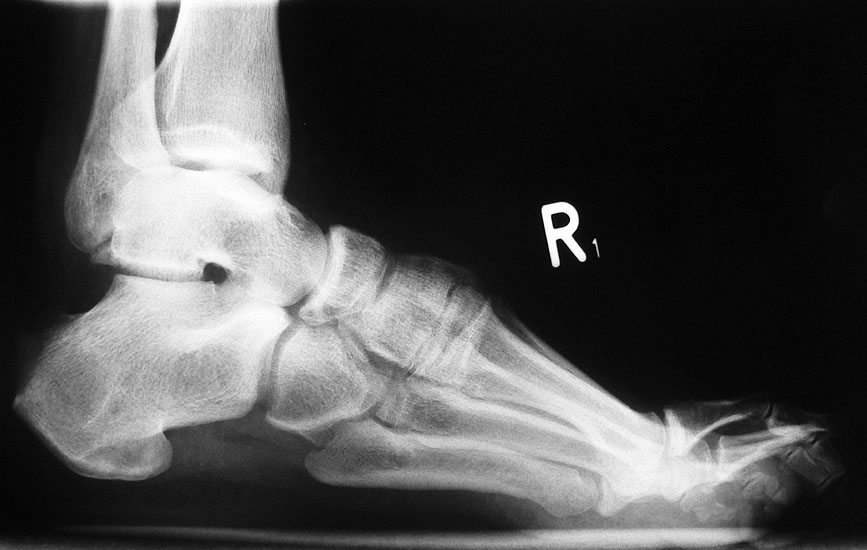

• Fuß belastet dp und seitlich (Abb. 14 und 15)

• Saltzman view (Abb. 16)

Typische Merkmale der Standard-dp-Röntgenaufnahme des Fußes im Stand

• Talus und Calcaneus verlaufen fast parallel

• Os naviculare ist gegenüber dem Talus nach medial gedrängt

• Metatarsalia überlappen sich basisnah

• Metatarsale I erscheint verkürzt

• Metatarsus adductus

Typische Merkmale der Standard-Seitaufnahme des Fußes im Stand

• Knöchelgabel ist außen rotiert

• Sinus tarsi ist einsehbar

• Subtalare Gelenklinie verläuft horizontal und ist breit einsehbar

• Der Abstand Malleolus medialis zum Os naviculare ist verkürzt

• Der Calcaneus erscheint verkürzt

• Der Krümmungsscheitel des Fußes ist erhöht

• Calcaneus pitch ist meist erhöht, der Rückfuß Equinus ist eher selten 12